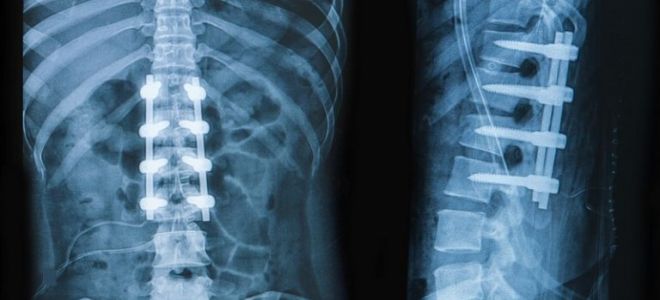

Постановка диагноза начинается с осмотра больного, в ходе которого выявляются специфические видимые дефекты строения шейного отдела позвоночника. Наличие сопутствующих деформаций осевого скелета или неврологической симптоматики также указывает на развитие недуга. Для подтверждения проблемы используются визуальные методы. Рентген – наиболее доступная техника диагностики синдрома Клиппеля-Фейля. Снимки делаются в двух проекциях, самой информативной является боковая. При этом полученные фото не позволяют оценить состояние спинного и головного мозга. Для визуализации этих структур используется компьютерная и магнитно-резонансная томография. В большинстве случаев исследования являются обязательными, поскольку их результаты используются как для дальнейшего прогнозирования течения недуга, так и при подготовке к операции. Перед тем как начать лечить патологию требуется также оценка функции внутренних органов. Данная необходимость связана с широкой распространенностью сопутствующих аномалий. С этой целью проводится УЗИ, осуществляются анализы крови и мочи.

- Уменьшение количества шейных позвонков, что укорачивает данный сегмент осевого скелета. Структуры срастаются между собой. Это обуславливает изменение их нормальной подвижности. Нарушения хорошо видны на рентгенограммах.